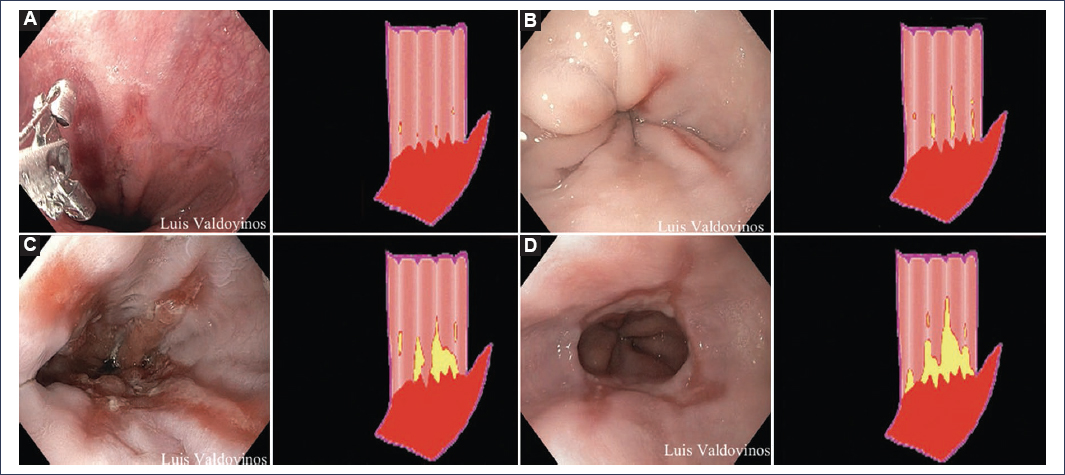

Endoscopy has been used as a fundamental diagnostic tool, as it allows an objective evaluation of the esophageal mucosa. In the context of GERD diagnosis, erosive esophagitis, Barrett’s esophagus > 3 cm, and peptic stricture are considered specific findings3. For the characterization of erosive esophagitis, the Los Angeles classification constitutes a widely validated and highly useful instrument, as it allows a systematic evaluation of mucosal lesions. This classification divides esophagitis into four grades according to the extent and location of the observed lesions13,14:

- ‒ Grade A: one or more mucosal breaks ≤ 5 mm, not crossing the folds13 (Fig. 1). Does not establish the definitive diagnosis of GERD15.

- ‒ Grade B: one or more mucosal breaks > 5 mm, not crossing the folds13 (Fig. 1).

- ‒ Grade C: one or more mucosal breaks that cross the folds, but involving < 75% of the esophageal circumference13 (Fig. 1).

- ‒ Grade D: one or more mucosal breaks that cross the folds and involve > 75% of the esophageal circumference13 (Fig. 1).

Figure 1. Los Angeles Endoscopic Classification (A-D).

Currently, the presence of Los Angeles grade B, C, or D esophagitis is considered diagnostic of erosive GERD. Grade A esophagitis is no longer considered a diagnostic criterion for GERD because asymptomatic patients may present this finding on endoscopy; however, those with suggestive symptoms, grade A esophagitis, and abnormal esophageal exposure by pH monitoring or pH-impedance monitoring are diagnosed with non-erosive GERD4,13.